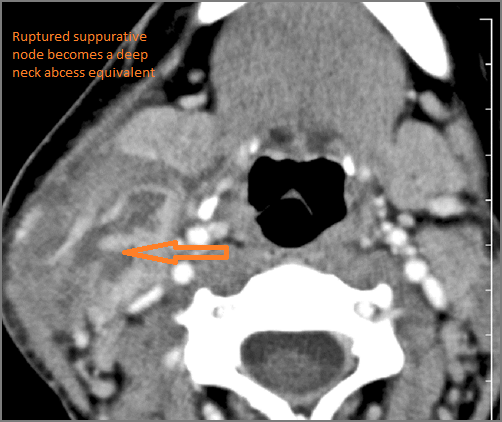

There is suppurative retropharyngeal lymphadenopathy.

If there is suppurative cervical adenopathy thepurulent material outside the lymph node(s) capsule(s).